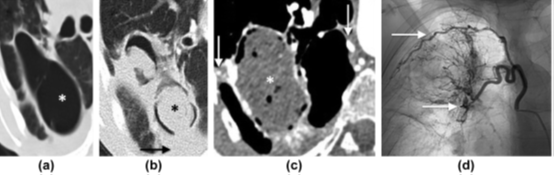

3. 形成空洞最常见的支气管来源恶性肿瘤是鳞状细胞癌(图1),其次是腺癌和大细胞癌。形成空洞最常见的转移性肿瘤同样是起源于头颈部或盆部、食管的鳞状细胞癌,其次是腺癌(图1)。

图1 (a)不规则厚壁空洞(*),右肺上叶后段支气管闭塞(箭头)。病理:差分化鳞状细胞癌。(b)子宫内膜癌切除术后,右肺尖空洞(箭头),双肺多发大小不等结节(*)。(c)双肺弥漫性含空洞结节(箭头),符合转移。(d)经甲地孕酮治疗后,病灶洞壁变薄(箭头)。

2. 曲菌球是在原有空洞基础上发生二重感染形成的,由菌丝、炎性细胞、纤维蛋白和碎片组成(图5)。曲菌球若边缘光滑,一侧与空洞壁之间形成新月形透亮区,称“空气新月征”。邻近胸膜增厚是一个早期征象,出现时间比曲菌球早3年左右。气液平面、空洞内完全填充及钙化较少见。无强化结节、附近有支扩、已有肺基础病变、随体位改变移动可作为与恶性空洞性病变的鉴别点。50%~80%的患者并发支气管动脉增粗,这可能引起致命性的大咯血(图5)。

图5 曲菌球形成。a)右肺上叶较大空洞(*),壁薄。(b)洞壁增厚,与腔内肿块(*)形成“空气新月征”,邻近胸膜增厚(箭头)。(c)2年后,成熟曲菌球形成,增粗的肋间动脉和支气管动脉间形成侧支循环(箭头),后经血管造影证实(d)。